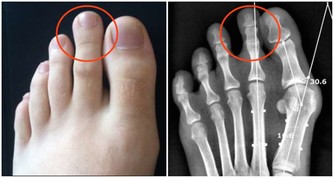

2、勺型、非勺型和深勺型三種類型血壓:

勺型血壓:是指夜間較白天血壓下降10-20;

非勺型血壓:是指正常部分人群中其夜間血壓並無明顯下降,或者夜間血壓下降不到10;

深勺型血壓:指的是部分人群夜間血壓過度下降,大於20以上,這類型高血壓患者心、腦、腎併發症的發病機率較高,但其具體意義還有待於更多的研究證實。